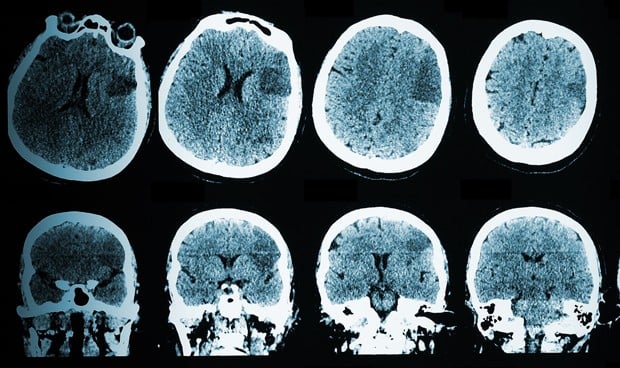

Los autores del estudio describen una red epiléptica de 320 genes, llamada M30, que está asociada con la enfermedad; en concreto, han concluido que los genes de la red determinan la forma en que las células cerebrales se comunican entre sí y que, cuando falla, desencadena la epilepsia.

Al parecer, la red funciona mal en la epilepsia de origen genético, y también en la provocada por una lesión cerebral, la que se desarrolla después de un accidente cerebrovascular o incluso la causada por una infección.